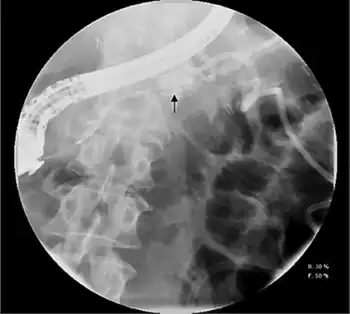

Pleural or ascitic fluid should be sent for analysis. An elevated amylase level, usually > 1,000 IU/L, with protein levels over 3.0 g/dL is diagnostic. Serum amylase is often elevated as well, due to enzyme diffusion across the peritoneal or pleural surface.[1][2] Contrast-enhanced computed tomography and endoscopic retrograde cholangiopancreatography (ERCP) may also assist in diagnosis, with the latter an essential component of treatment.